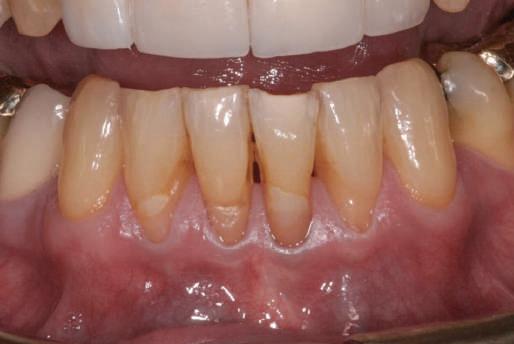

Reprepararea intraorală a bonturilor Acest pacient prezenta dentiţia maxilară compromisă, refuzând proteza mobilizabilă. Prin abordarea în etape, se menţin o parte din bonturile dentare naturale; s-a observat recesie în momentul amprentării pentru cel de-al doilea grup de implanturi.

Fig. 1 prezintă pacientul după inserarea primului set de bonturi implantare individualizate; dinţii naturali adiacenţi

sunt încă prezenţi pentru a susţine puntea provizorie.

Şapte luni mai târziu (fig. 2), acele bonturi individualizate din prima etapă au manifestat semne de recesie de 1-3mm. Atitudine: S-a decis reprepararea intraorală a tuturor bonturilor (fig. 3), astfel încât toate marginile bonturilor să fie la nivelul sau sub marginea gingivală (de notat că 1.1. şi 2.1. au fost submersaţi ulterior pentru a avea sprijin implantar deplin).

Deşi reprepararea a îmbunătăţit marcat estetica finală, a necesitat aplicarea şnurului de retracţie, amprente noi şi turnări noi.

Un caz separat dar similar ilustrează în figurile 4 și 5 reprepararea intraorală a bontului.

Cazul (1): Reprepararea intraorală a bonturilor Figurile

1. Aspect după inserarea primului set de bonturi implantare individualizate.

2. După 7 luni, bonturile individualizate din prima etapă au prezentat recesie de 1-3mm.

3. Bonturile repreparate intraoral.